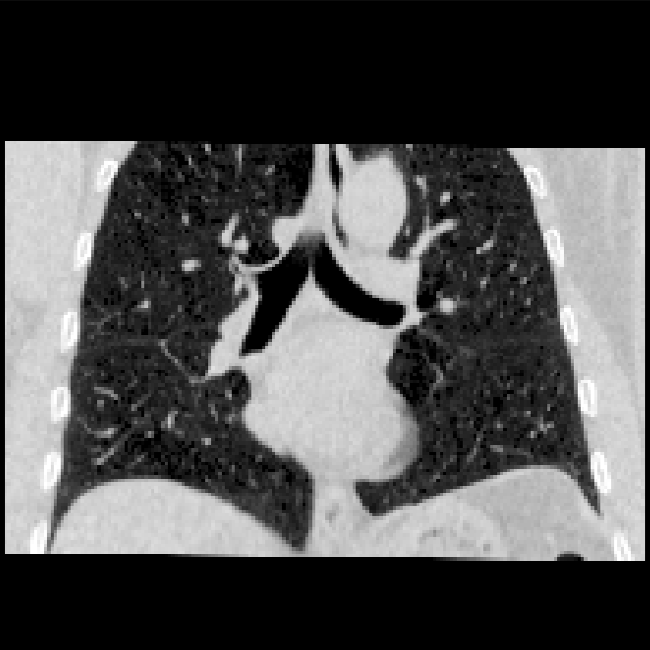

Lung CT

The aim of the lung CT task was the registration of expiration to inspiration CT scans of the lung. Establishing correspondences between longitudinal lung scans can help to monitor disease progression, estimate motion in radiotherapy planning or enable direct assessment of lung ventilation. The data consists of 20 training [33] and 10 test scan pairs [34]. The scans were acquired at the Dept. of Radiology at the Radboud University Medical Center, Nijmegen, NL. All pairs were affinely pre-registered and resampled to an image size of 192×192×208192192208192{\times}192{\times}208. Lung segmentation masks and keypoints were provided as additional training information. The complexity of this registration task is manifold. First, the fields of view of the fixed and moving scan differ largely since the lungs in the expiration scan are not fully visible. Second, the scale of the motion within the lungs can often be larger than the anatomical structures (vessels and airways) themselves. Therefore, a registration method needs to estimate large displacements that account for substantial breathing motion and also align small structures like individual pulmonary blood vessels precisely. To measure the accuracy manual landmarks are used that are typically located at the boundary or bifurcation of vessels, airways, and parenchyma.